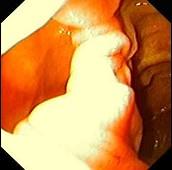

女性,45岁。腹部饱胀不适2年余。表情自然,皮肤无黄染,未见蜘蛛痣,巩膜无黄染。腹平坦,腹肌软,全腹无压痛反跳痛,肝脾肋缘下0.5cm,胃镜检查如下图,诊...

问题 女性,45岁。腹部饱胀不适2年余。表情自然,皮肤无黄染,未见蜘蛛痣,巩膜无黄染。腹平坦,腹肌软,全腹无压痛反跳痛,肝脾肋缘下0.5cm,胃镜检查如下图,诊断为 ( )

选项 A.十二指肠憩室 B.十二指肠溃疡 C.十二指肠炎 D.十二指肠穿孔 E.十二指肠雍滞症

答案 A